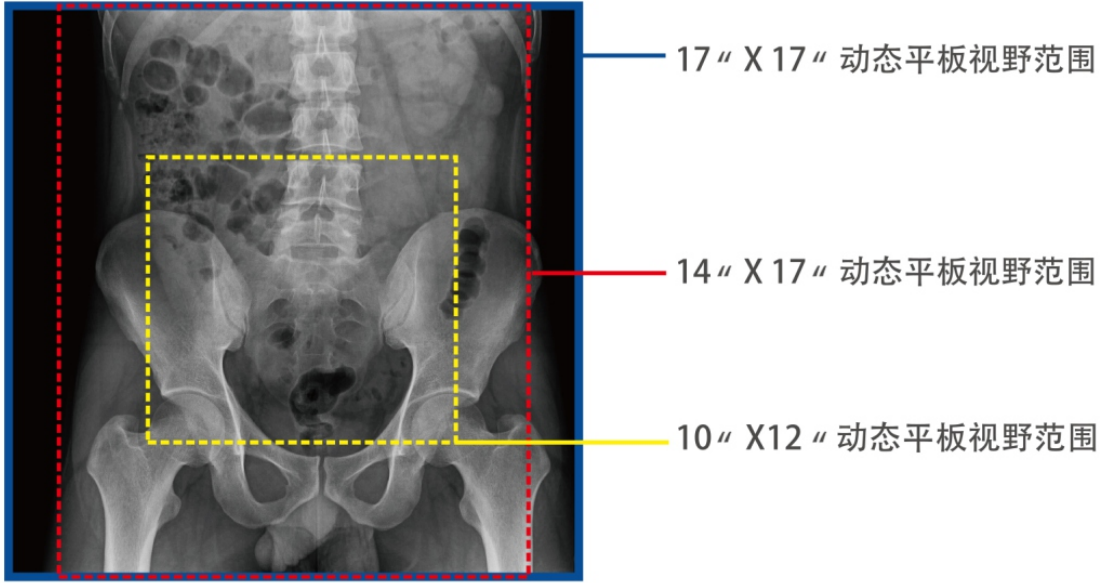

3、大尺寸平板探測(cè)器

1)能對(duì)患者的胸部腹部等部位實(shí)現(xiàn)大范圍全覆蓋,透視檢查無(wú)需對(duì)患者重新定位便可觀察到足夠大的人體器官組織,避免漏診誤診。